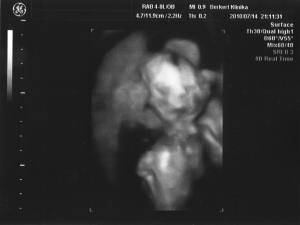

Vivi! kis zsarnok